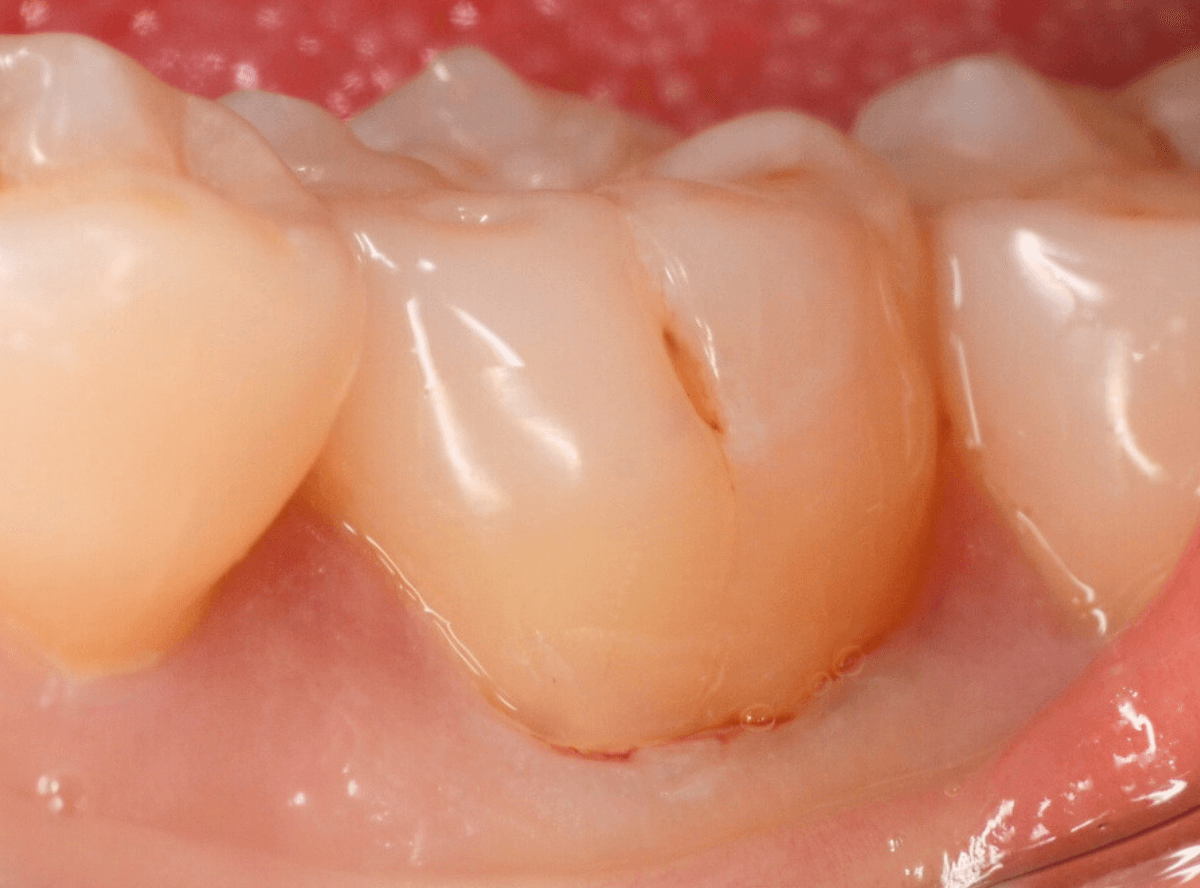

実際の治療例

Case.5

今回も「奥歯がしみる」という訴えで来院された患者さんのケースです。

「以前に通っていた歯医者さんで知覚過敏と診断され、薬を塗って様子をみていたが、最近痛くなってきた。」

との事でした。

お口の中を拝見すると、奥歯が二本、側面がえぐれていて、そっと風をかけると飛び上がるほどしみるようでした。

以前の先生に受診された時の詳細な状況はわかりませんが、この状況ではおそらくお薬を塗っても厳しいと感じ、レジンで側面をつめる処置をする事になりました。

今回もしみる症状が強いため、麻酔をして、えぐれている部分にレジンをつめて経過観察します。

あとは、経過観察で症状が改善される事を祈るしかありません、症状も強かったため、これで改善されなかった場合は、歯の神経を除去する治療も考える必要もあります。

→後日来院時、劇的に改善されたとの事でした。

ただし、歯ブラシ圧でこの部分のレジンは簡単に外れてしまいます。十分注意するように磨き方も指導しました。